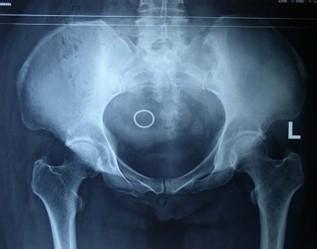

检查诊断:检查者一手压住直腿侧髂嵴,另一手握住屈腿膝盖部并下压,如果患者臀部出现疼痛,可能是患有骶髂关节炎,该项检测被称为“4”字试验。X线检查可见骶髂关节的破坏性改变。确诊为:骶骼关节炎。